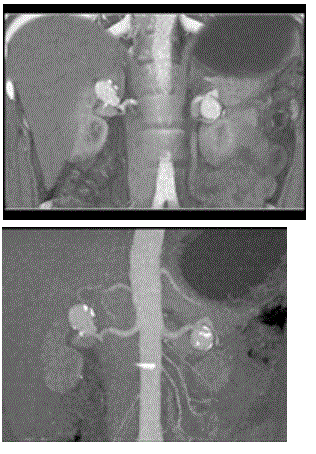

问题 男,32岁,偶然发现有高血压,请结合图像,作出最可能诊断( )

选项 A、双侧肾动脉狭窄 B、双侧肾动脉夹层动脉瘤 C、双侧假性肾动脉瘤 D、双侧肾动脉出血血肿形成 E、双侧肾动脉瘤

答案 E